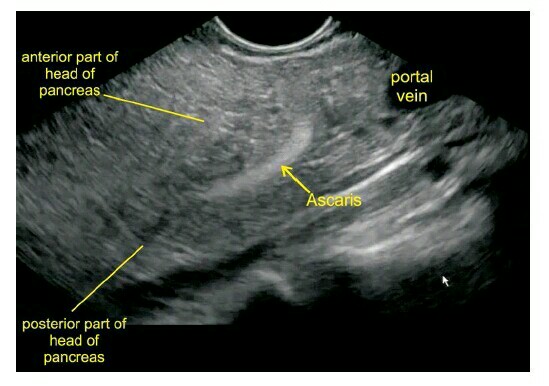

患者,女性, 35 岁,因剧烈腹痛 伴呕吐就诊,腹痛可放射至背部。查体发现体温高,腹部压痛明显,实验室检查示白细胞计数、淀粉酶及脂肪酶升高,诊断为「急性胰腺炎」,行超声内镜(EUS)明确胰腺炎病因。EUS 见胰腺肿大,胰管内有一线状高回声结构,不伴有声影(图 1)。